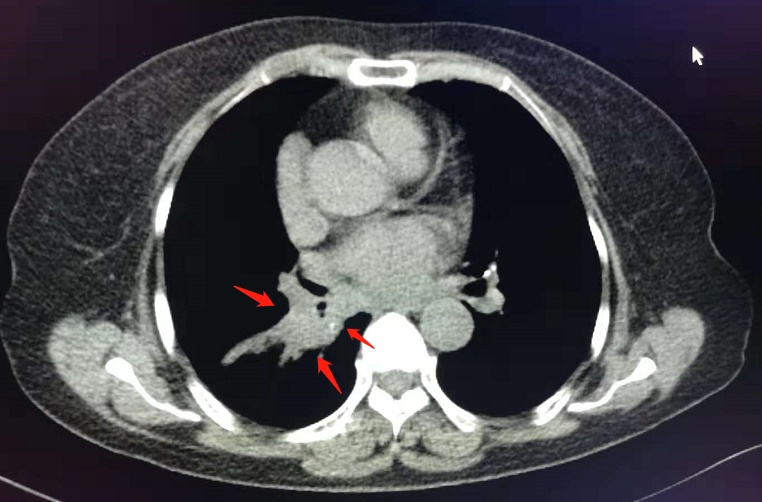

像这位女士,因为晚期肺癌剧烈胸疼,而且广泛黏连大血管,已经不能手术。

通过放射性粒子植入,既缓解疼痛,改善生活质量,也延长了寿命。